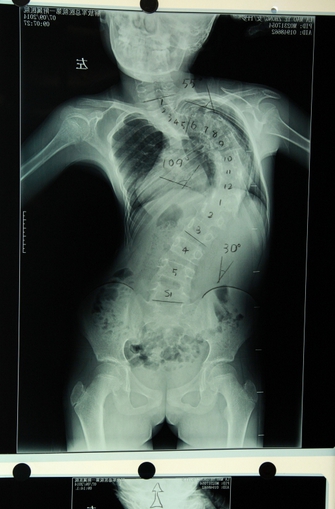

拉毛叶忠3岁时发现有脊柱侧后凸畸形,由于从小失去父母,无钱医治,一直没有治疗,侧凸畸形已超过120度,同时伴有105度的后凸畸形。近年来,由于脊柱畸形越来越严重,已经13岁的拉毛叶忠身高仅有110厘米,比同龄孩子要矮小很多。不仅严重影响正常发育和生活,而且多脏器受到挤压,经常疼痛难忍,呼吸功能受到严重损害。7月7日,由青海塔尔寺阿卡更登彭措带着到解放军总医院第一附属医院求治。

拉毛叶忠手术示意图

拉毛叶忠严重变形的脊柱